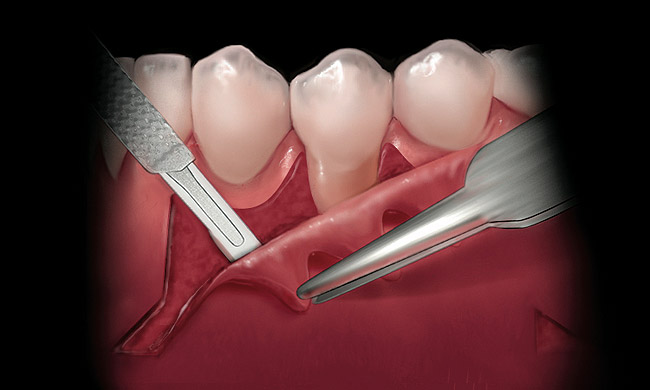

A local anesthetic should be administered mesially and distally of the intended surgical site. A sulcular incision is then started one tooth distal to the tooth/teeth to be treated. The incision is continued to the opposing side one tooth from the site requiring treatment. The papilla should be spared and left attached to the lingual soft tissue to help eliminate soft tissue loss interproximally. Vertical releasing incisions are next made bilaterally and carried beyond the mucogingival junction, ending in Burrow’s triangles (Figure 1). A Burrow’s triangle is used to relieve tension at the most apical extent of a vertical releasing incision to improve flap mobility and achieve tension-free closure.9

The Burrow’s triangle is then grasped by a tissue forceps and a split thickness dissection with a 15C blade is accomplished to remove this tissue (Figure 2).10 Using a 15C scalpel blade and holding the flap margins with tissue forceps, a split thickness flap is reflected past the mucogingival junction (Figure 3).

Figure 1  Incisions illustrated with Burrow’s triangles located apical to the mucogingival junction.

Figure 1

Figure 2  While grasping the tissue at the center of the Burrow’s triangle, a scalpel is used to excise it.

Figure 2

Figure 3  While grasping the flap margin with an Addison forceps, a scalpel is used to create a partial thickness flap.

Figure 3